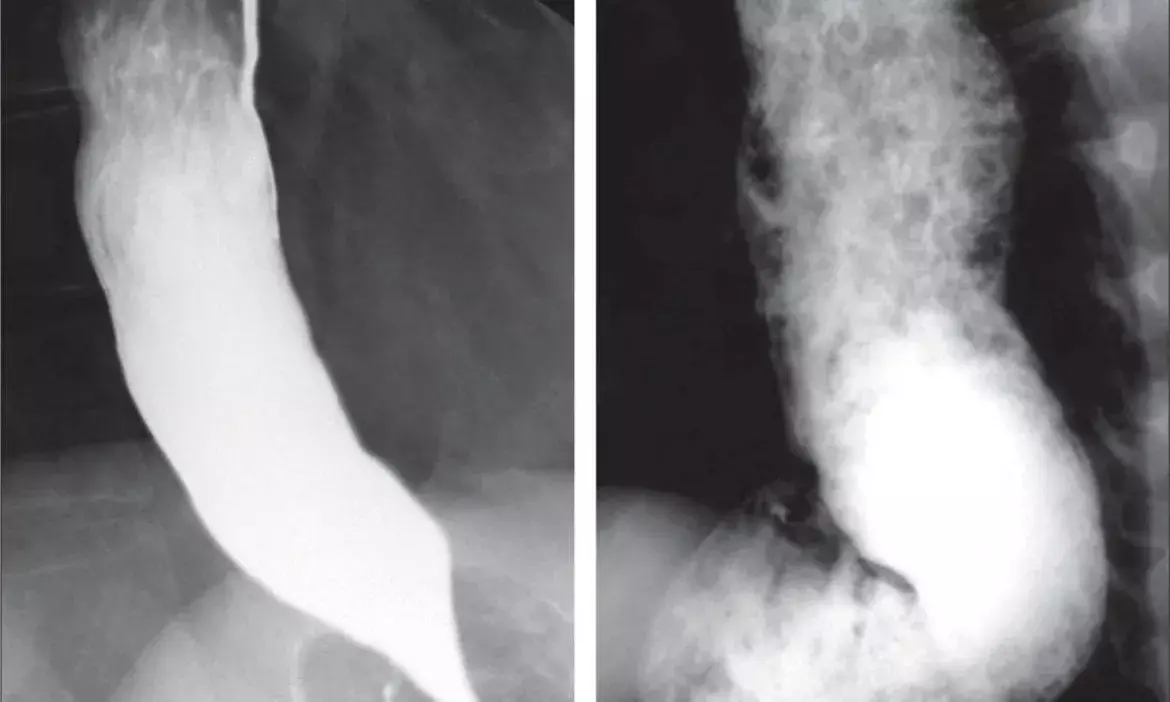

Hyderabad: Docs at KIMS perform rare endoscopic surgery on boy who was unable to swallow solid food